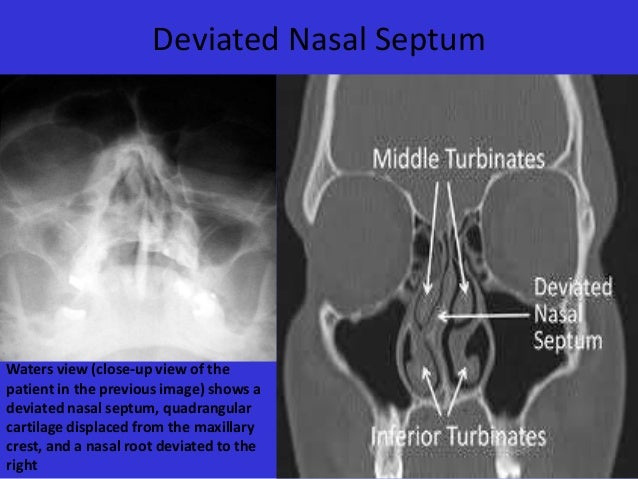

The external nose consists of paired nasal bones and upper and lower lateral cartilages. Internally, the nasal septum divides the nasal cavity into a right and left side. The lateral nasal wall consists of inferior and middle turbinates and occasionally a superior or supreme turbinate bone.Nov 16, 2021